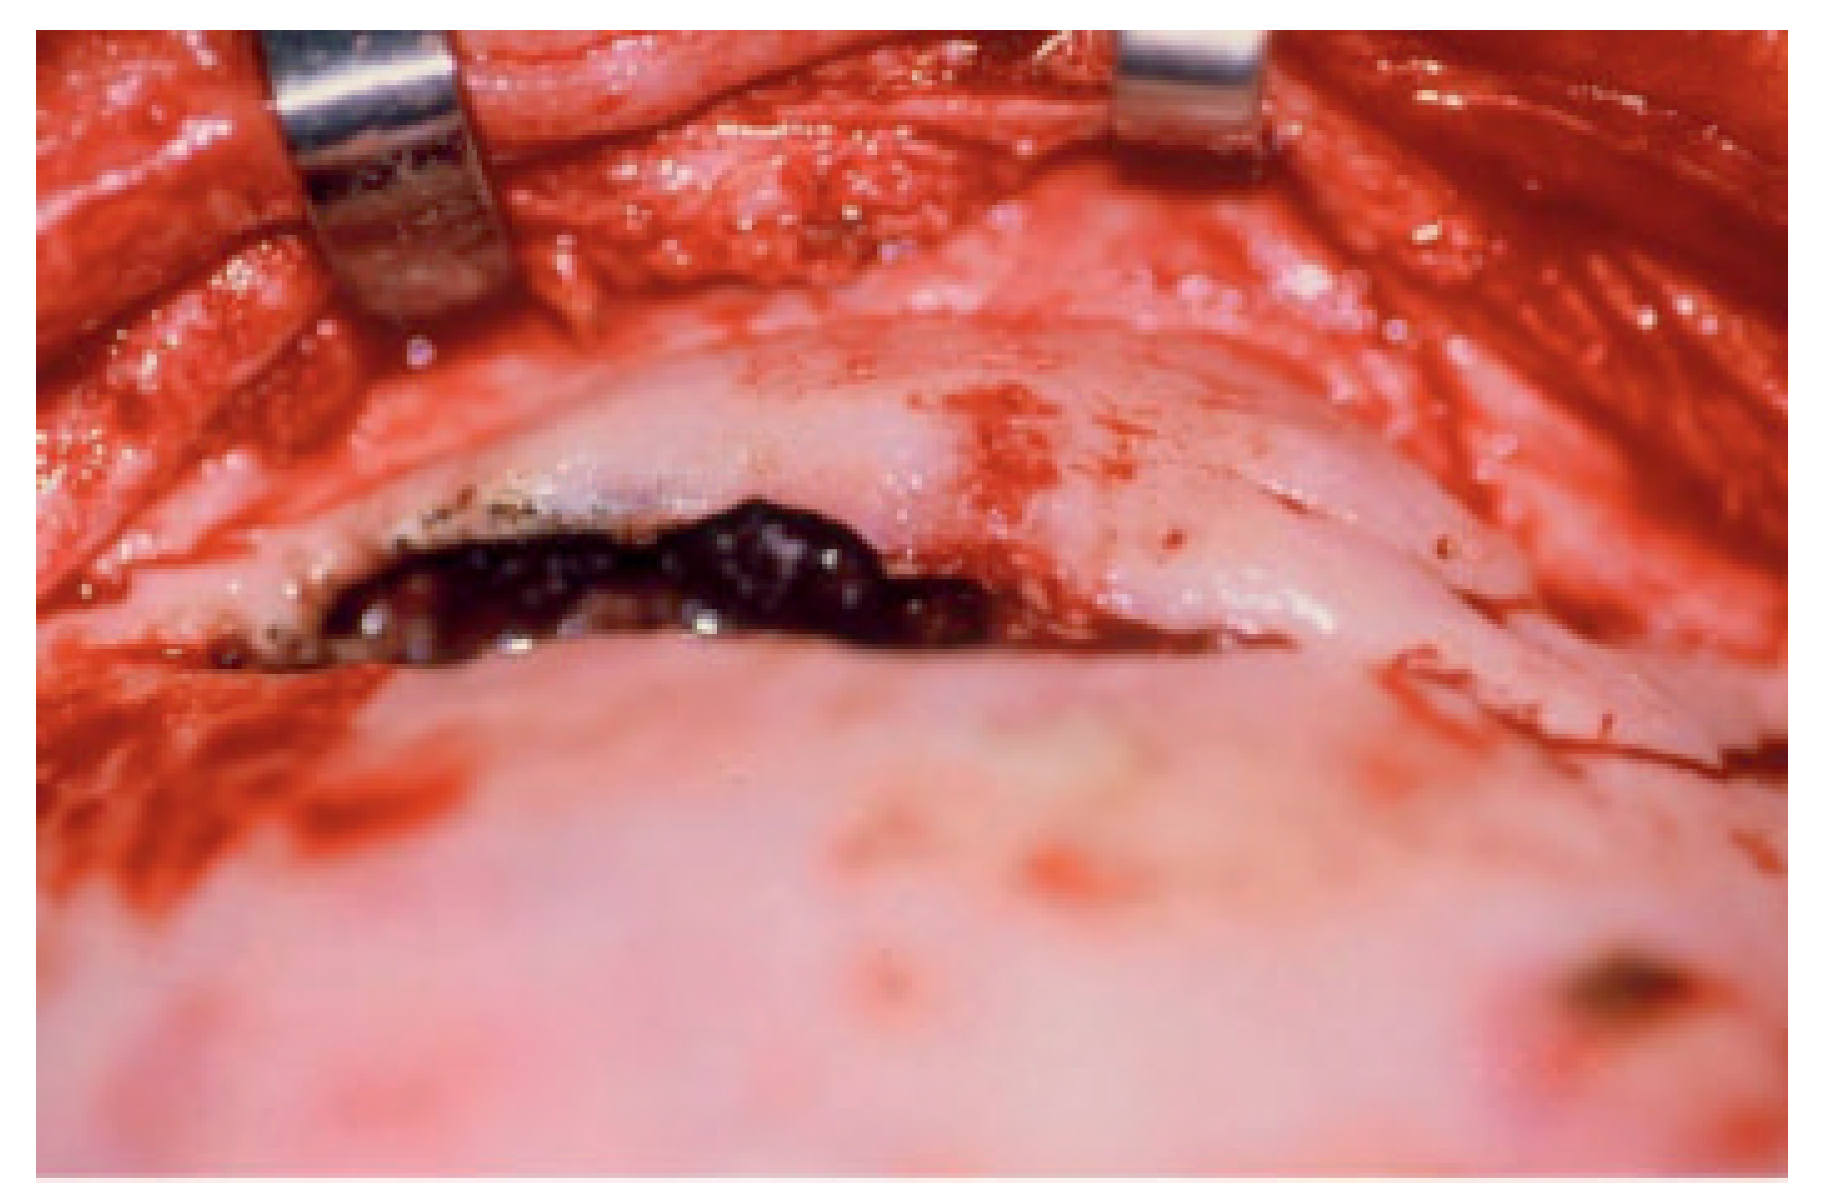

Disruption of the nasofrontal ostia or ducts is an important factor in the development of immediate and delayed complications after frontal sinus fractures (Figure 2) [8]. Combined fractures of the anterior and posterior table are almost always accompanied by injuries to the nasofrontal orifices [4,5,8]. Severity of the injuries is variable but can be predicted from the sinus wall fracture pattern and the mechanism of injury [4,8]. High-resolution computed tomography (CT) scanning as well as image-guided endoscopy can give sufficient information to predict a disruption of the drainage system, but there is nothing as good as direct visualization of the nasofrontal ostia [2,9,10]. Functional status can be estimated with fluorescein endoscopy; however, this may not always be accurate [3,10,11,12]. Successful management of frontal sinus fractures depends on correct diagnosis of structural pathology, which may lead to inflammatory or infectious complications. When in doubt, it is better to separate the anterior skull base from the nasal cavity. We believe this is best accomplished with vascularized tissue (Figure 3) [2,13,14].

Figure 3.

Placement of a well-vascularized pericranial flap for separation of the anterior skull base from the nasal cavity. The ducts are plugged with temporalis muscle after thorough mucosal removal, and the pericranial flap is tucked in and secured with fibrin glue.